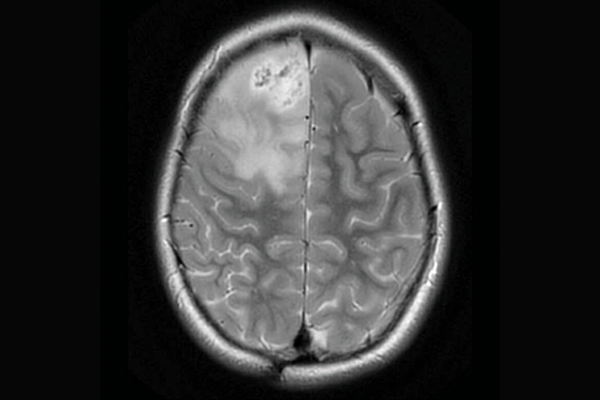

High-grade gliomas are a group of aggressive brain tumours and one of the deadliest tumours in children and young adults. In some children, the tumours are driven by mismatch repair deficiency (MMRD), which is characterized by hypermutation (a large and quickly accumulating number of mutations in tumour cells) and resistance to standard treatments such as chemotherapy and radiation.

priMMRD-1: The ultra hypermutant

These tumours are the most common, with 62 per cent of tumours having both MMRD mutations and polymerase proofreading deficiency (PPD), making them extremely sensitive to immunotherapy. A first-in-kind clinical trial called U-R-Immune Glioma, led by Drs. Eric Bouffet and Das at SickKids, is already pursuing an immunotherapy-first approach for these patients, sparing initial radiation therapy.